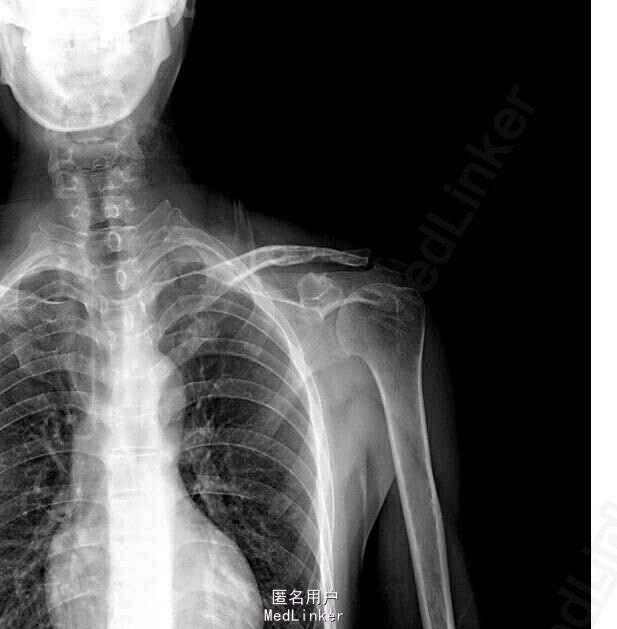

左锁骨远端骨折术后8月余。 患者八月余前因外伤致左锁骨远端骨折,于我院在全麻下行左锁骨远端骨折切开复位内固定术,术后恢复可。2月余前,患者复查锁骨正位X线片提示骨折已牢固愈合。现术后8月余,患者左肩功能尚未完全恢复,为取出内固定物再次入院

步入病室,左锁骨区可见一长约7cm陈旧手术瘢痕。局部及左胸锁关节区触痛、压痛(-),左肩关节活动受限,外展上举约70°。左锁骨正位X线片检查:左锁骨远端骨折术后,骨折愈合。

诊断:左锁骨远端骨折术后 行左锁骨远端骨折术后内固定物取出,左肩关节手法松解术